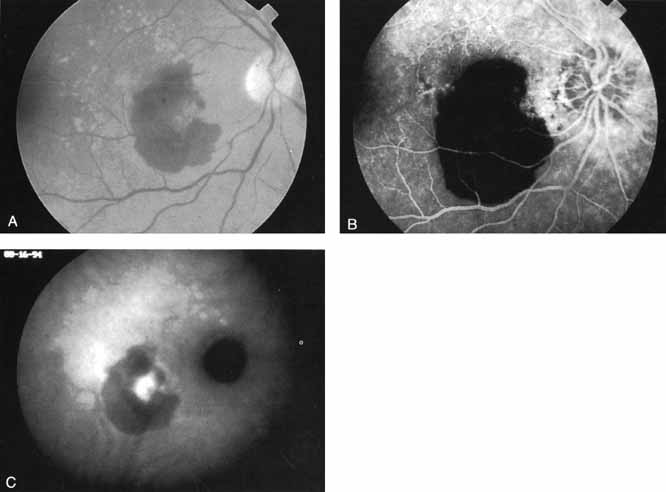

With this clinical diagnostic and histopathologic information available, pilot studies were performed to determine the practicality of using ICG angiographic guidance in the treatment of occult CNV. Slakter and associates28 performed laser photocoagulation treatment on 79 eyes with occult CNV. The occult CNV was successfully eliminated in 57% of patients who underwent ICG-guided treatment (Figs. 5 and 6). The authors found the success rate to be higher (66%) for patients with CNV not associated with PEDs than for those with PEDs (43%). Visual acuity improvement or stabilization was achieved in 57% of all patients. Recurrences were more frequent and more difficult to control in those patients who had associated PEDs on initial clinical presentation. Additional independent studies have reported similar diagnostic and treatment outcomes with the use of ICG angiography in patients with occult CNV.29,30

Sorenson and colleagues31 reported on the diagnostic and therapeutic ability of ICG angiography in patients who had clinical signs of recurrent CNV but who were found to have occult membranes on fluorescein angiography. In a group of 66 patients, 97% were identified as having localized areas of hyperfluorescence on ICG angiography consistent with recurrent CNV (Fig. 7). In laser photocoagulation treatment performed in a subgroup of 29 patients, 62% achieved anatomic resolution and stabilization of the exudative process over time. Visual acuity improved in 66%, 45% of whom achieved a visual acuity of 20/100 or better.